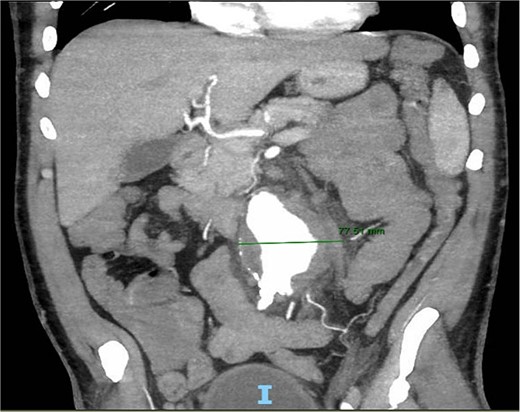

A 56-year-old male with no reported past medical history and a 70 pack year smoking history presented with a chief complaint of lower abdominal pain and body aches. On presentation, the patients white blood cell count (WBC) was 39.6 and procalcitonin was 43.4. Blood cultures were drawn and demonstrated P. mirabilis bacteremia. Computed tomography (CT) abdomen/pelvis was performed as well as ultrasound (US) of scrotum demonstrating a complex fluid collection within scrotal sac that was determined to be a scrotal wall abscess. The patient was started on a course of Unasyn and Urology promptly took him to the operating room (OR) for incision and drainage. Vascular surgery was consulted due to an incidental finding of an abdominal aortic aneurysm on CT measuring 4.7 × 4.6 cm (Figs 1 and 2). The patient was evaluated by the vascular surgery team following his urological procedure and denied any history of abdominal pain or back pain. Physical exam was largely unremarkable however the patient’s bilateral toes were noted to have blue discoloration with motor and sensation intact. Outpatient follow up with routine US scans for the AAA was recommended. Ankle brachial index (ABI) as well as an echocardiography was ordered to further work up the patient’s dusky toes. On Day 2 of hospitalization, ABIs returned showing severe peripheral vascular disease (PVD) and the echocardiography ruled out endocarditis. At this time an angiogram was planned to further the patient’s PVD workup however this was deferred as the patient remained septic with a WBC of 30. Over the course of the next few days the patient refused antibiotics and remained septic with a WBC in the 20s. At this time his toes quickly deteriorated from dusky to dry gangrene. On Day 8 of hospitalization the patient remained septic and was now complaining of new onset mid-abdominal pain. Emergent CT showed AAA was now 7.7 × 7.8 cm with periaortic fat stranding concerning for impending rupture (Figs 3 and 4). The patient was taken emergently to the OR for open repair. Upon visualization, the abdominal aortic aneurysm was clearly infected with signs of impending rupture on the left lateral wall and purulent material including infected thrombus. Tissue was cultured however showed no growth, likely due to the fact that the patient had been on antibiotic therapy for a week at this time. Reconstruction with an aorto-biiliac bypass using rifampin-soaked dacron graft was performed. A piece of omentum was mobilized over the graft and the retroperitoneum was closed over it. The abdomen was left open for a return to the OR for a second look which showed no concerns for bowel ischemia, worsening infection or bleeding. On post-op Day 5 the patient was extubated, off pressor support, and transferred to the floor. The patient’s postoperative course was unremarkable except for bilateral toes demarcating to dry gangrene.

Frontal CT of the abdomen and pelvis demonstrating 4.79 cm AAA.